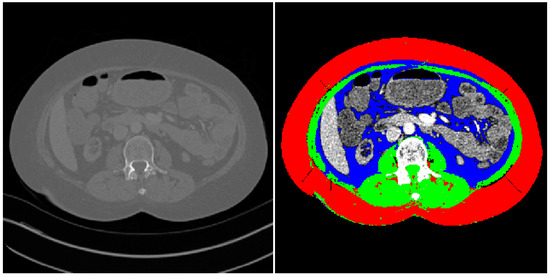

Sarcopenia was assessed using the semi-automated method previously described by Kim et al. [24]. Measurements were performed by two board-certified radiologists. The CT slice corresponding to the midpoint of the L3 vertebrae was identified and imported into the measurement application. The peritoneum was traced on these reference images to automatically identify skeletal muscle, visceral fat, and subcutaneous fat. All automated image analyses were prospectively assessed for accuracy to rule out miscalculations. Attenuation values of −29 to 150 Hounsfield units were assigned to identify muscle tissue (Figure 1).

Figure 1. A CT slice at the level of L3 used for assessment of sarcopenia. Points around the peritoneum were traced to enable segmentation of the imported CT slice (left) into the final image with a separating of skeletal muscle and visceral, subcutaneous fat (right). Red = subcutaneous fat, blue = visceral fat, and green = skeletal muscle.